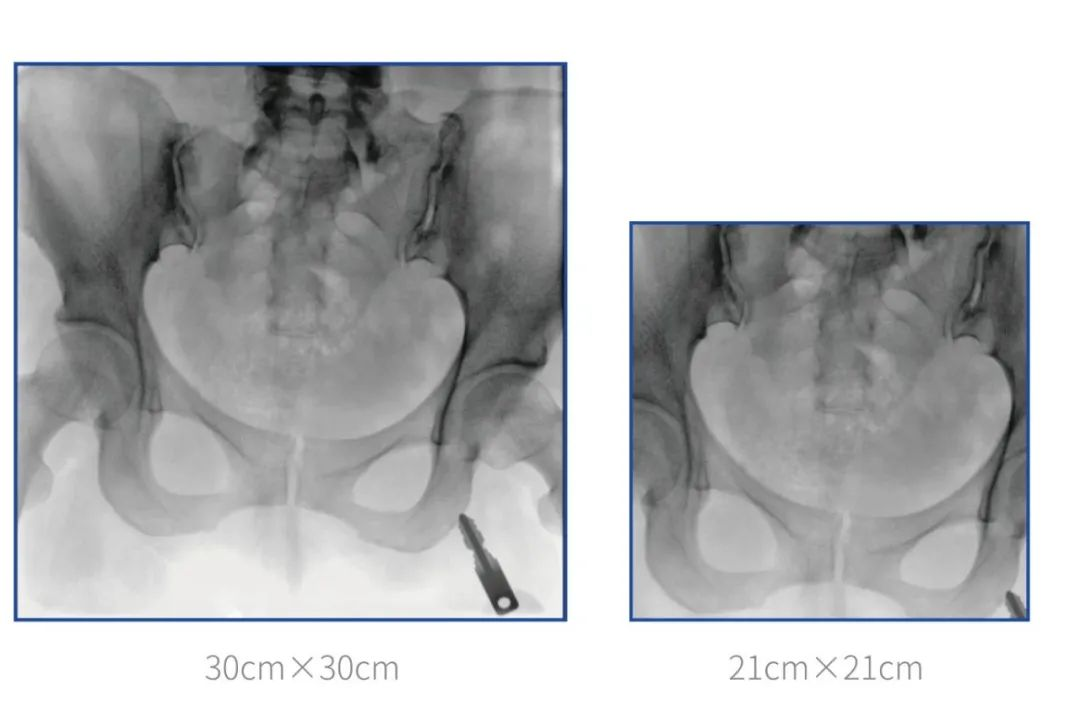

普愛醫(yī)療堅(jiān)持自主研發(fā)、持續(xù)創(chuàng)新,從臨床需求出發(fā),推出了大視野,能夠呈現(xiàn)更多圖像細(xì)節(jié)的大平板一體式C形臂。大平板一體式C形臂配置30cm×30cm平板探測(cè)器,對(duì)于諸如骨盆雙側(cè)骨折類型手術(shù)或骨盆后環(huán)內(nèi)固定術(shù)具有應(yīng)用優(yōu)勢(shì),一次曝光可獲取全部骨折部位影像,可簡(jiǎn)化曝光流程,提高手術(shù)效率!